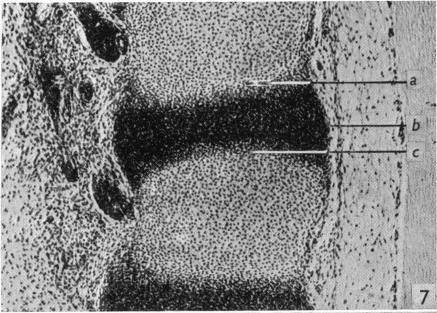

Observations on the prenatal development of the intervertebral disc in man.

J Anat. 1951 Jul;85(3):260-74.